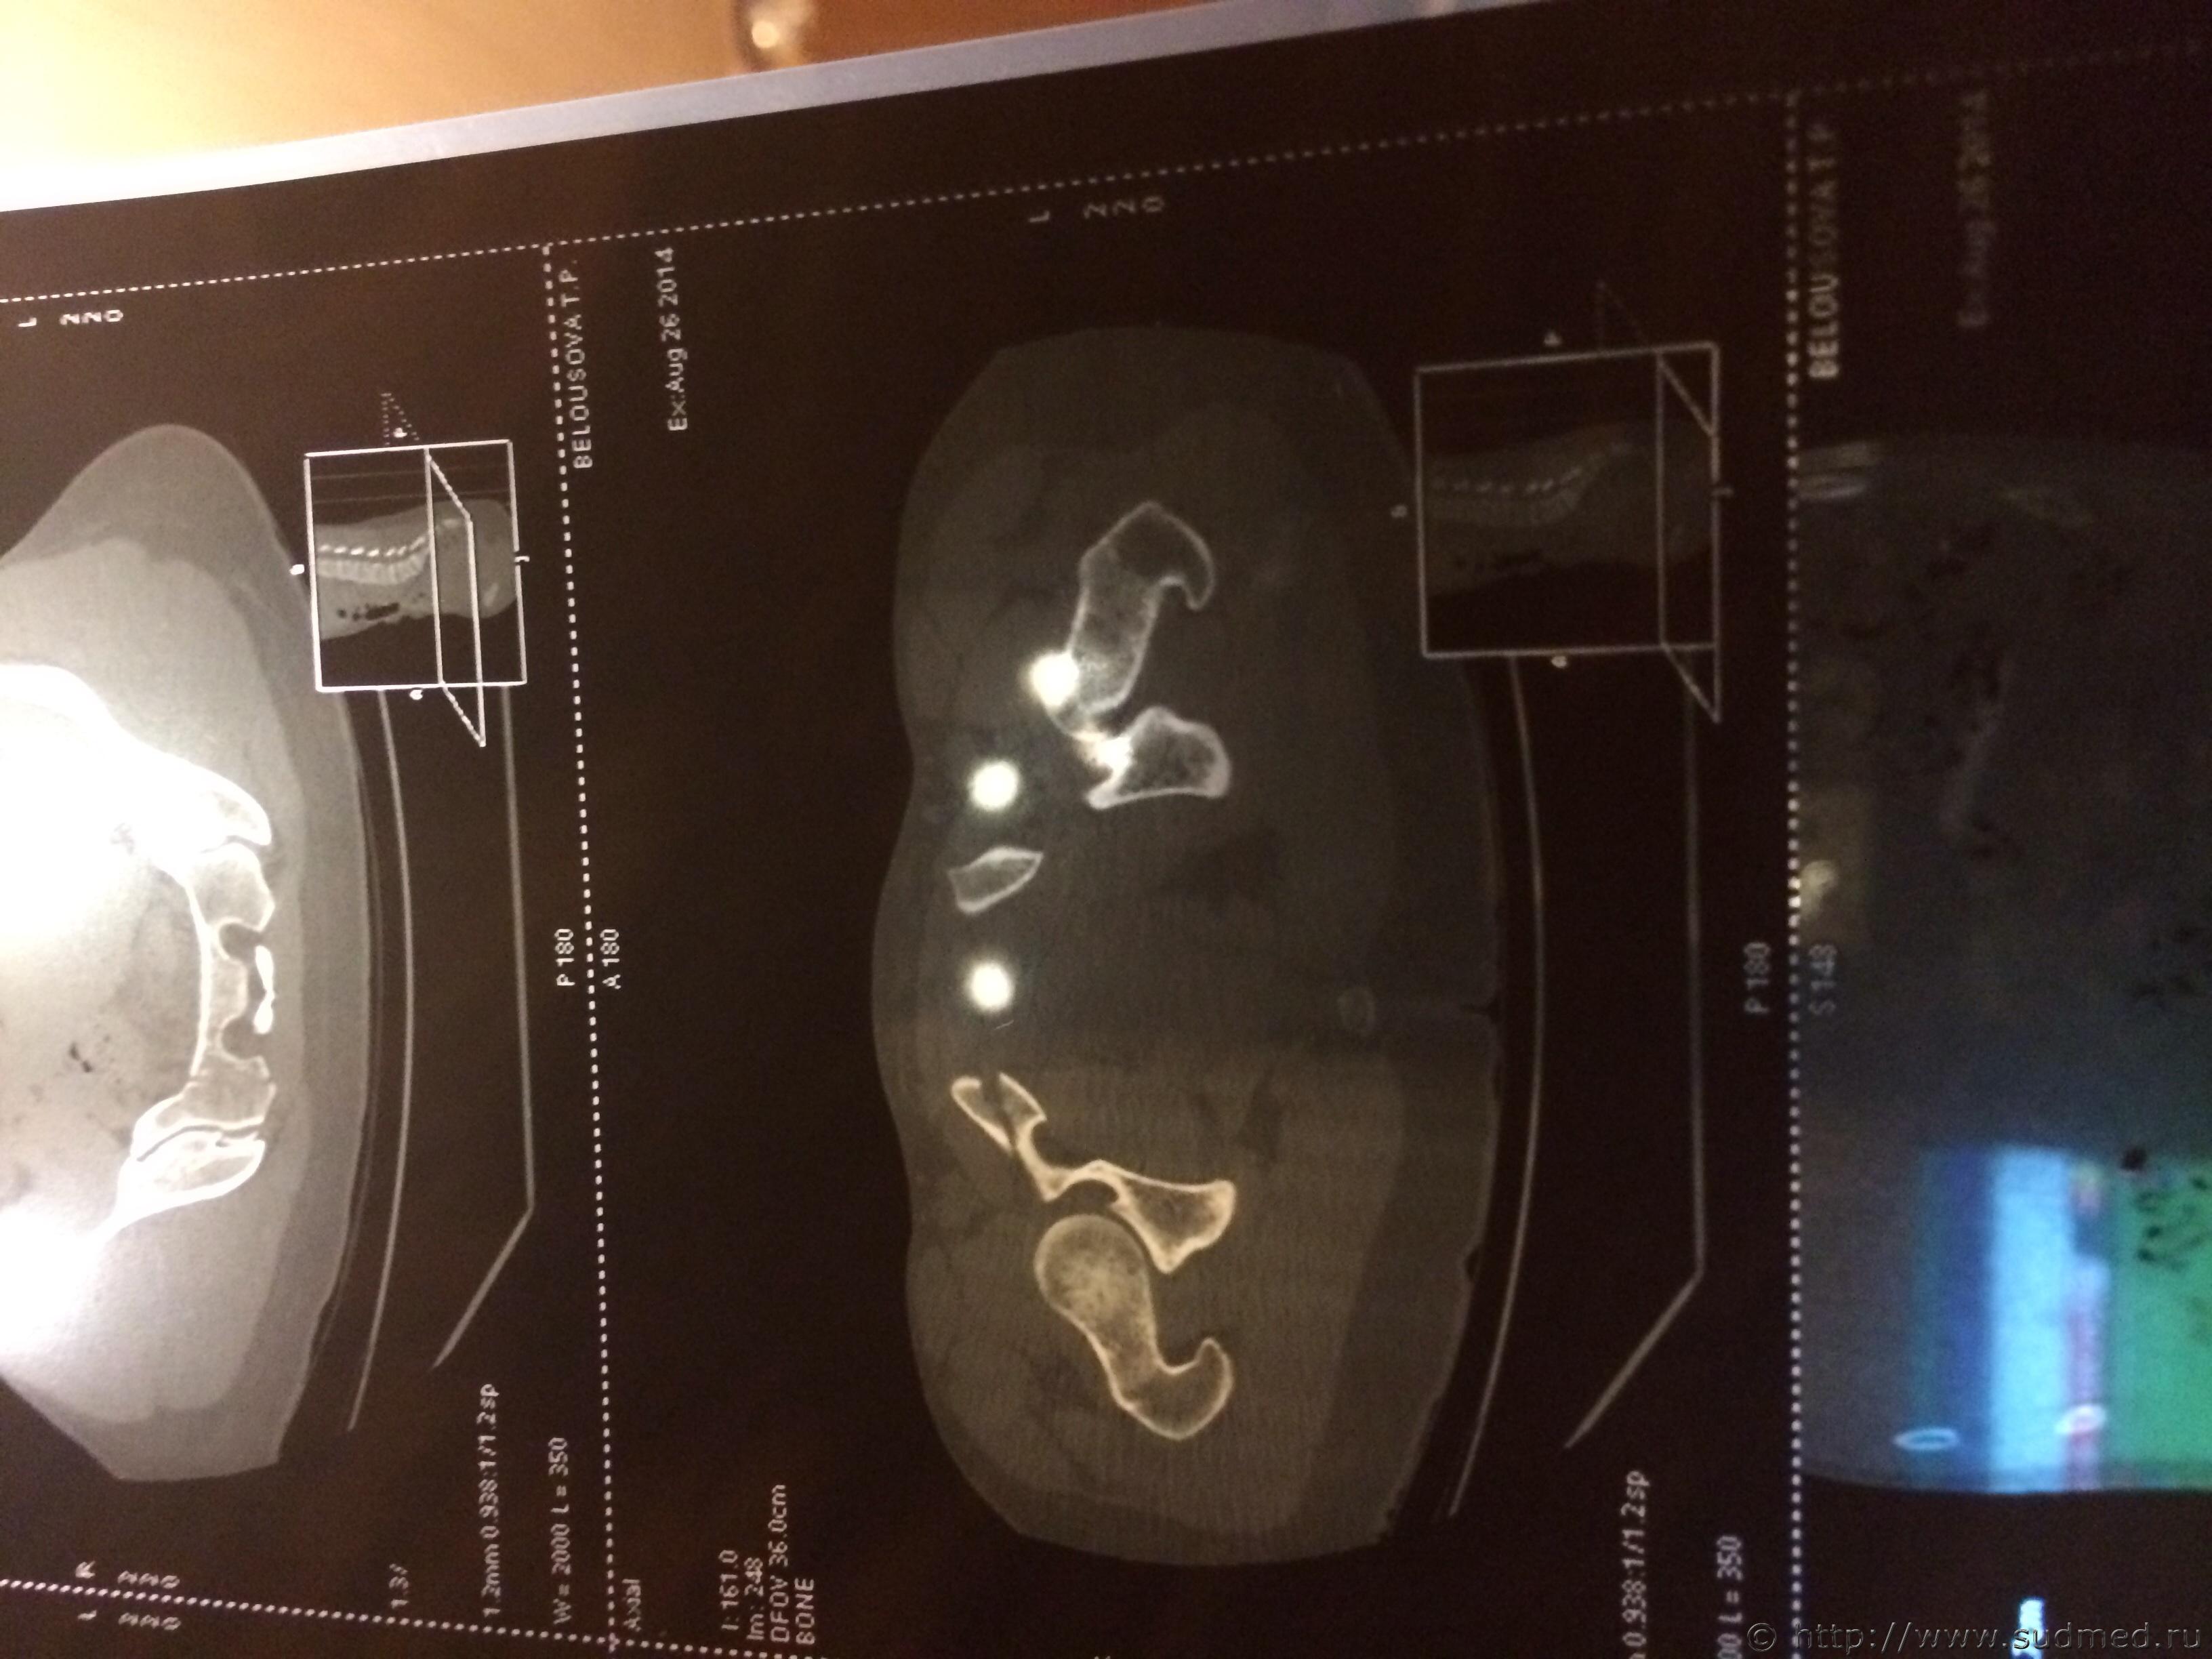

Спасибо! У меня результаты КТ, ошиблась)

КТ

Как мне видится - вертикальный перелом крестца. Тяжкий вред.

Впрочем, оставляю небольшую вероятность, что я не видел все сканы, да и качество их здесь, разумеется, хуже, чем изображение на пленке или на экране компьютера у врача, работающего на томографе.